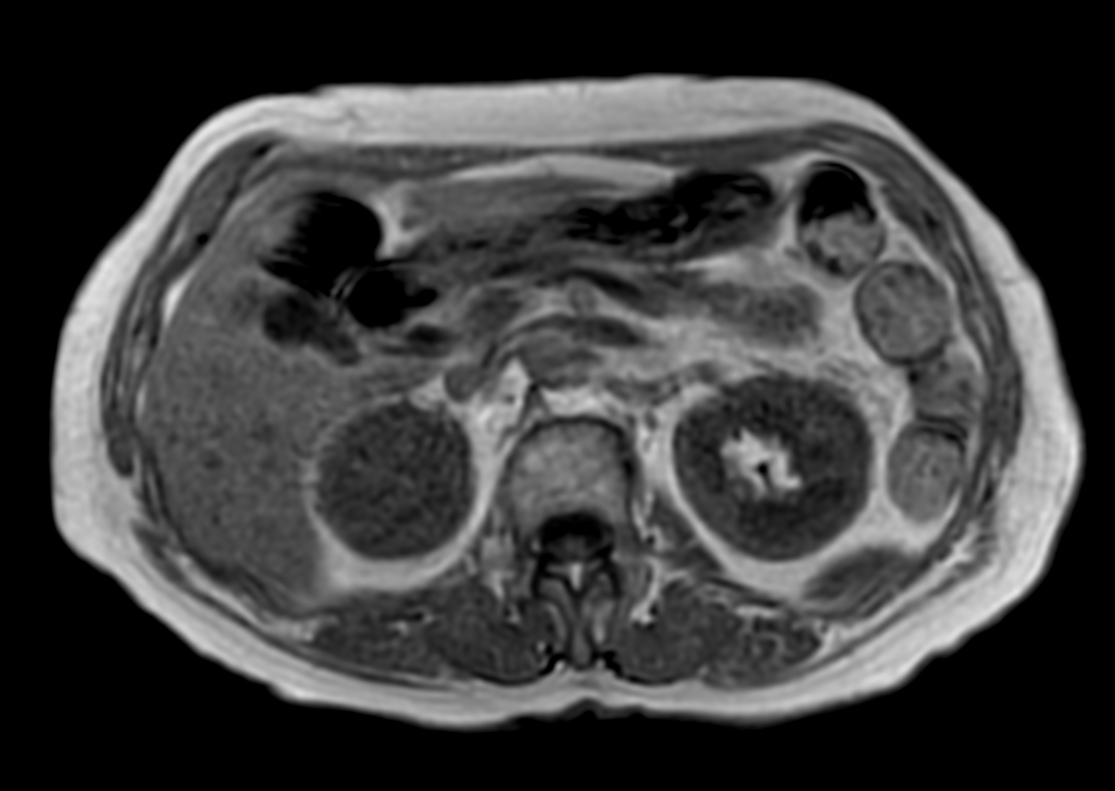

Patient with a kidney lesion. The ExamCard includes techniques for 3D imaging (PelvisVIEW, eTHRIVE) allowing for multiple image directions in one single scan, efficient fat-free imaging over large field-of-views (mDIXON XD), a multi-phase contrast-enhanced sequence (4D FreeBreathing) to improve imaging confidence and Compressed SENSE to accelerate the entire exam.

T2w TSE